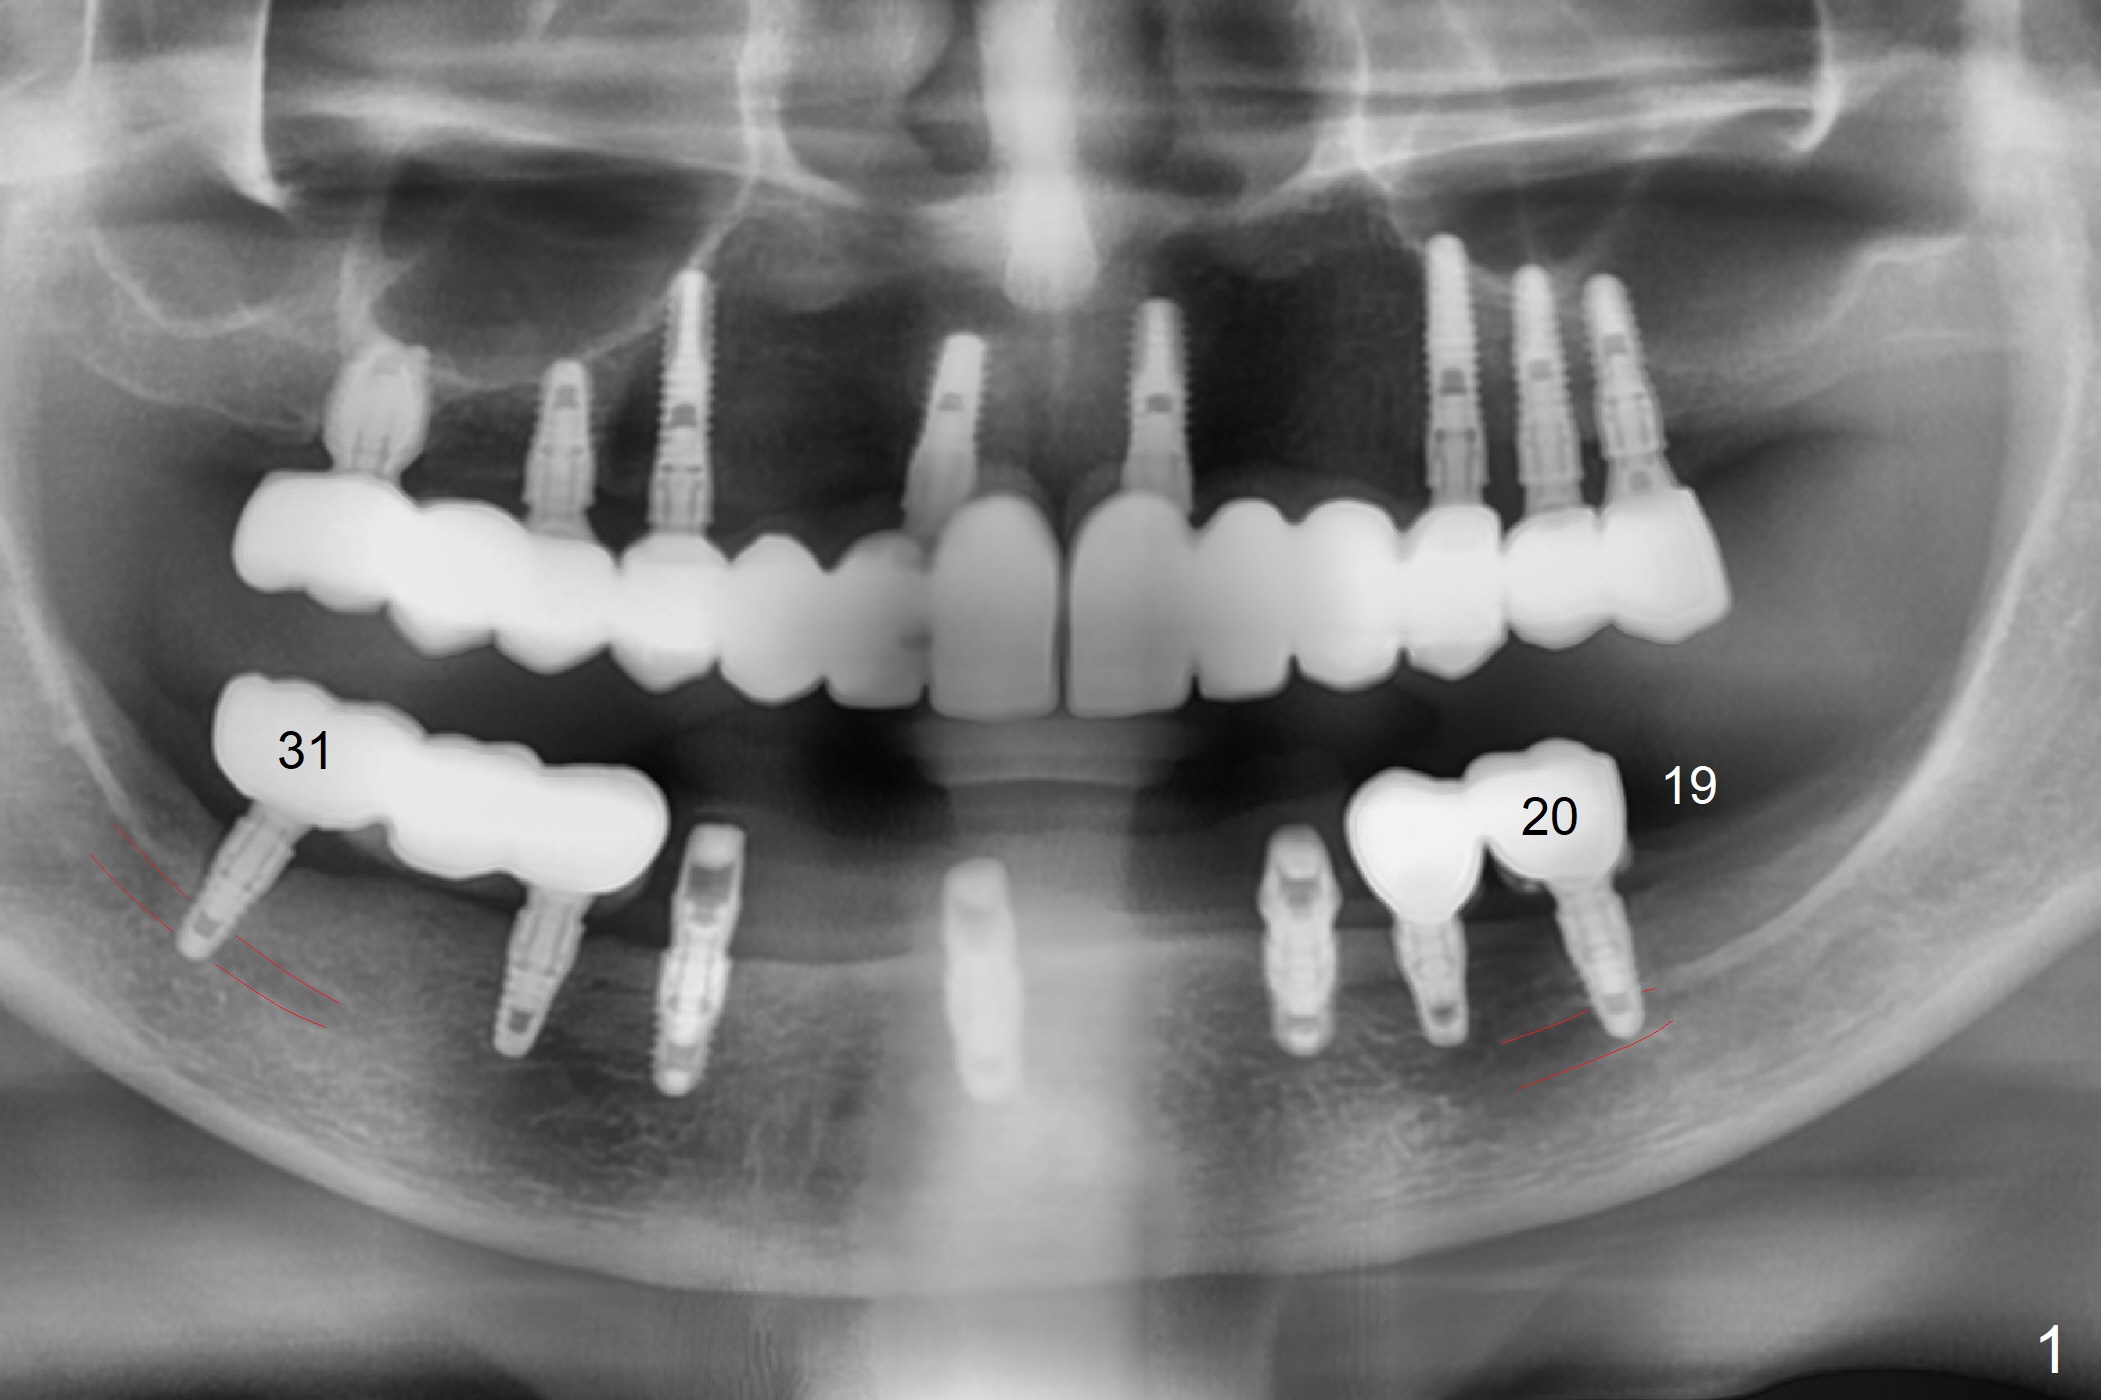

A 56-year-old woman with atrophic jaws requests redoing lower implant restoration (in function 1 year) for cosmetic reason and placing an implant at #19 (because she could not masticate on the left, Fig.1). While the 3.8x8.5 mm implants at #31 and 20 are placed lingual (L) to the Inferior Alveolar Canal (IAC, Fig.2,3) "free hand", can a 4x7.3 mm implant (Fig.4 blue outline) be placed buccally (B) at #19 with a guide?